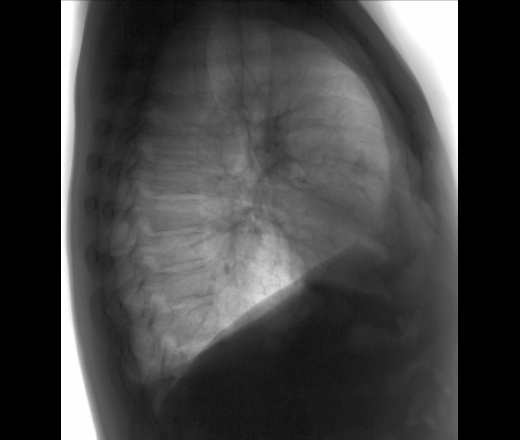

Мужчина 40 лет. Диагностическая  флюорография. Пришел на контроль, был поставлен диагноз 01.11.25 пневмония с\д, справа, в другой клинике. Смущает тень, которая видна только на задней проекции, в верхней доле справа, что это может быть? И еще, как считаете, есть выпот слева?

На левом боковом этой тени не видно